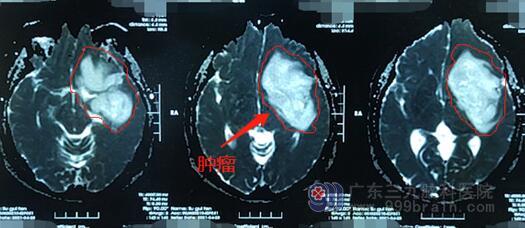

刘阿姨的磁共振检查提示:左侧额颞岛叶占位性病变,大小约80mm×48.1mm×50.6mm,考虑弥漫性星形细胞瘤可能性大。欧阳辉主任带领医师团队为刘阿姨制定了手术方案:为了避免术中损伤语言中枢和运动功能,要在唤醒麻醉下显微手术切除左侧额颞岛高级别胶质瘤。术前,主管医生给阿姨及她家属详细地讲解了手术方案及手术流程;护士们给阿姨送去了祝福卡片与鼓励,那一天刘阿姨的眼中不再是害怕,而是多一份战胜病魔的坚定。

▲术前

▲术后